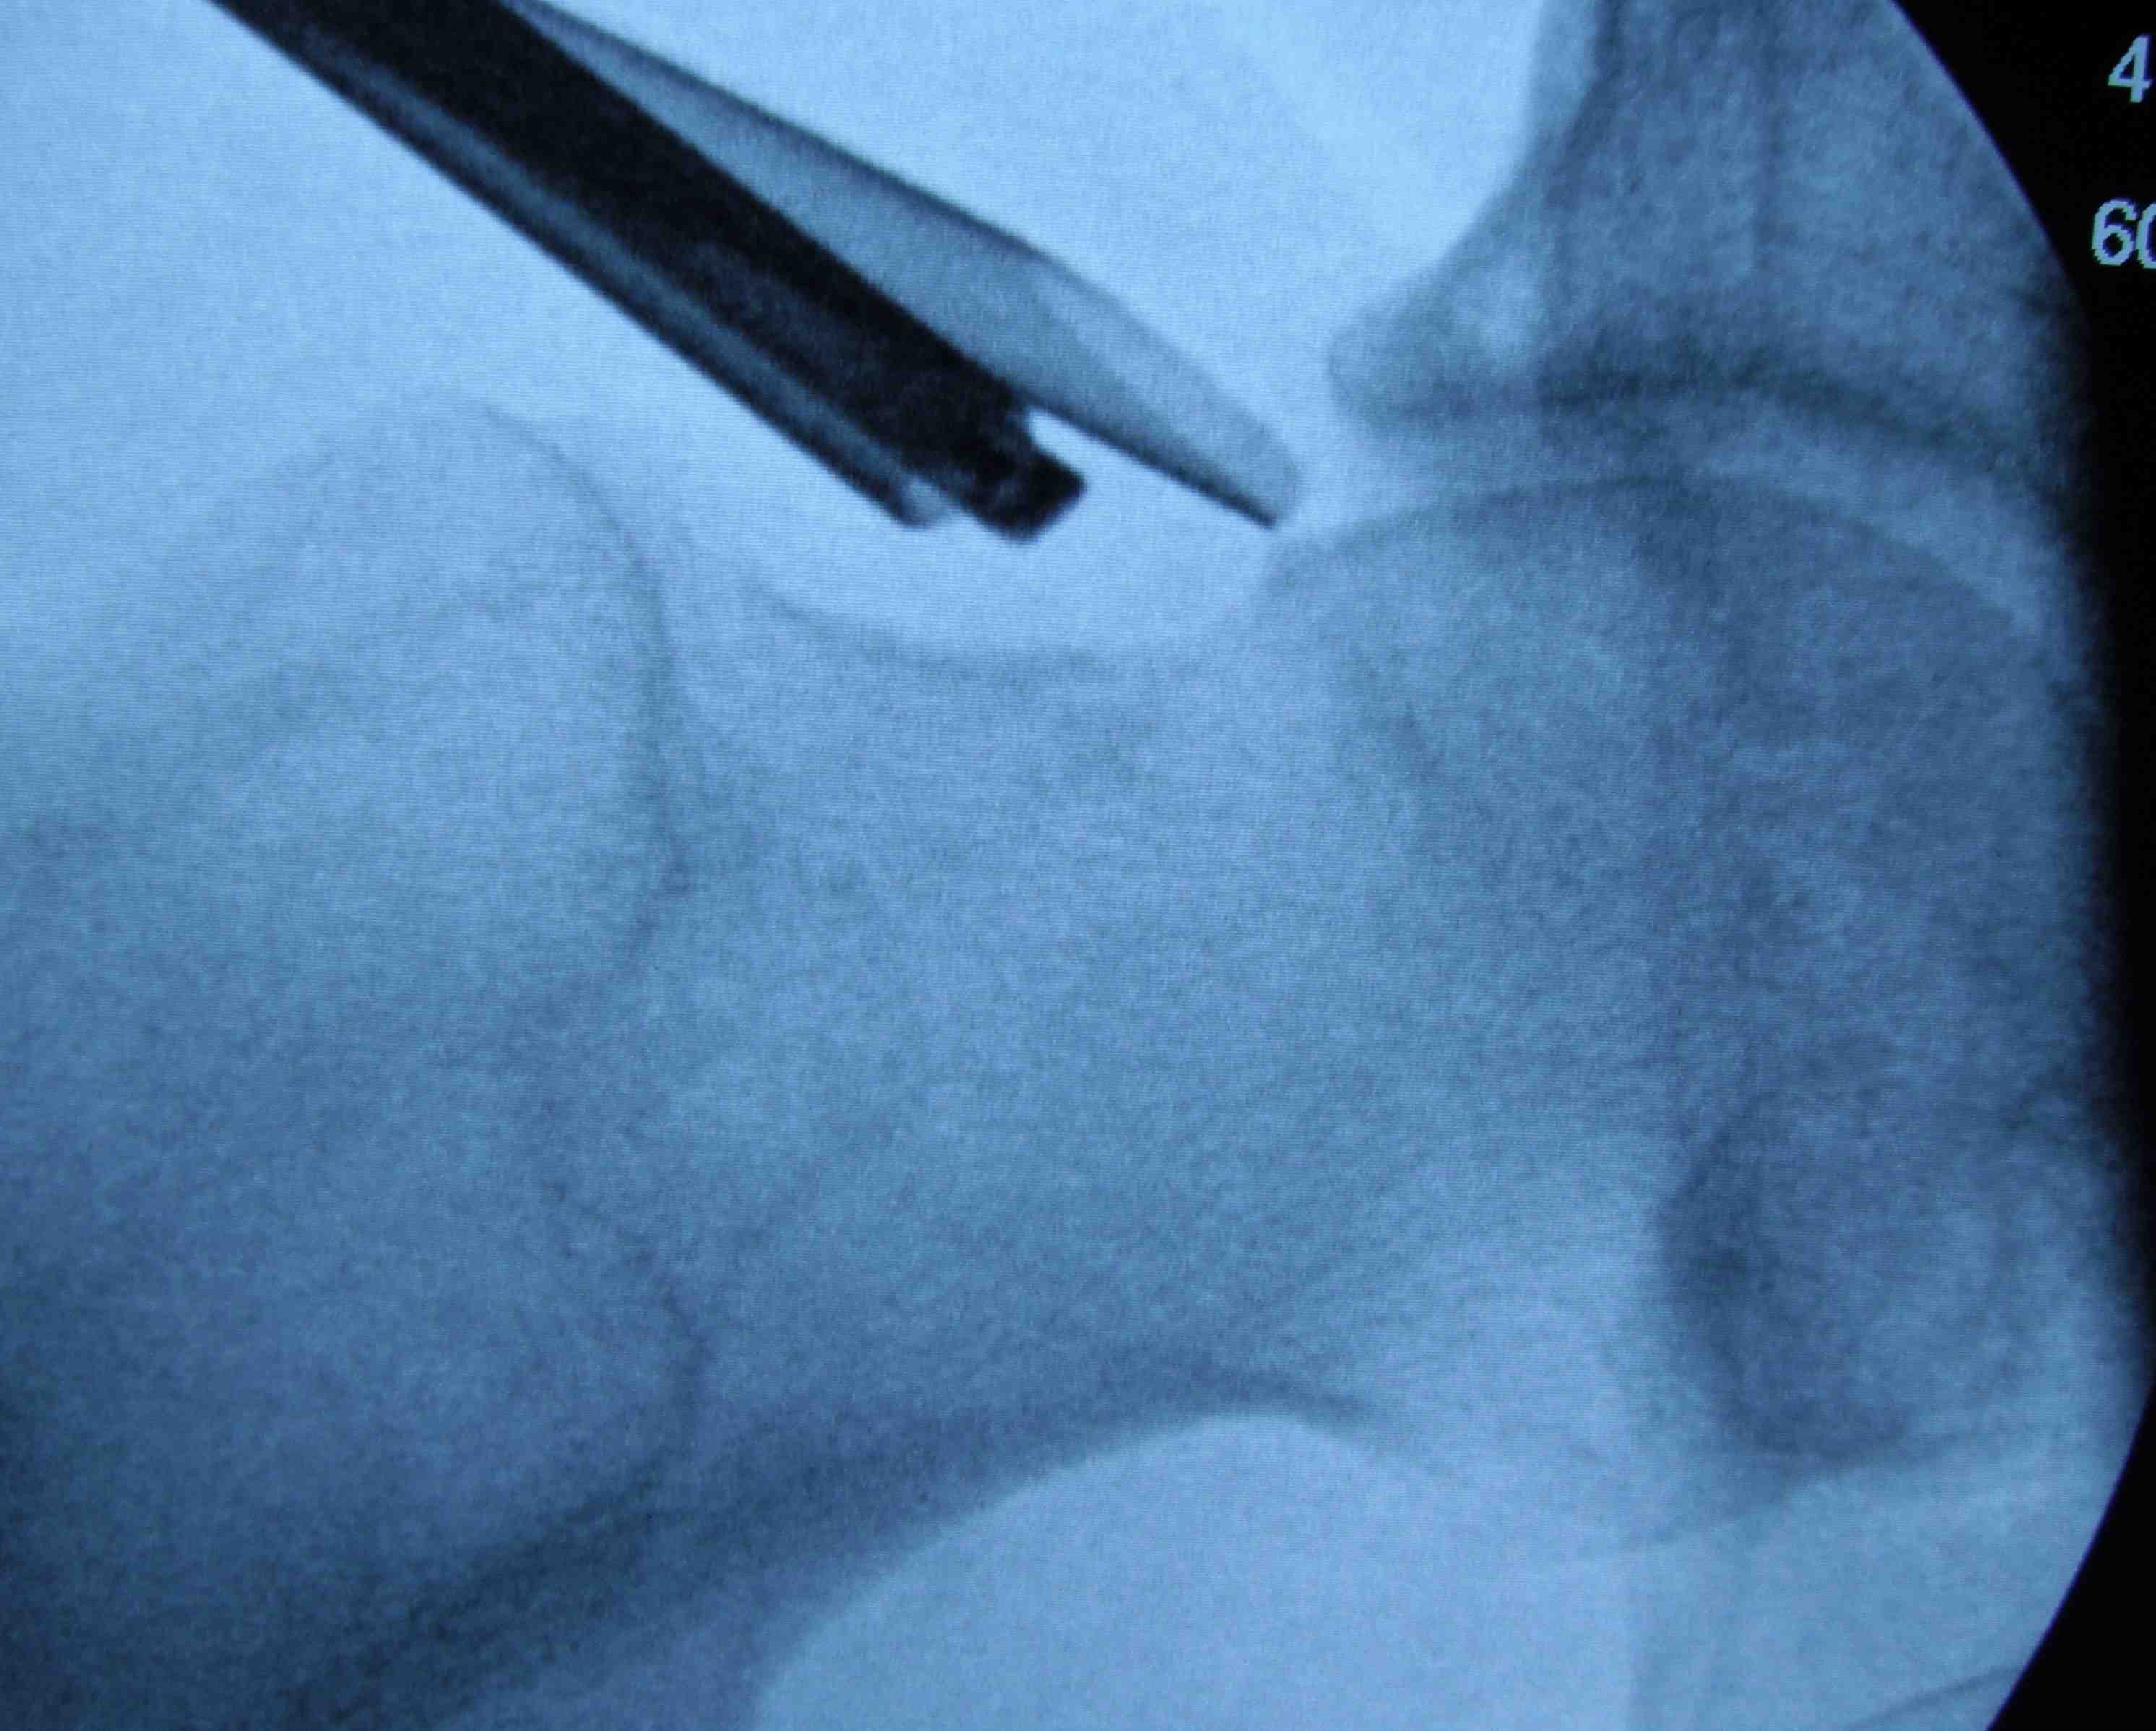

Anterior cam resection with hip flexed

Intra-operative Cam resection using Dunn view